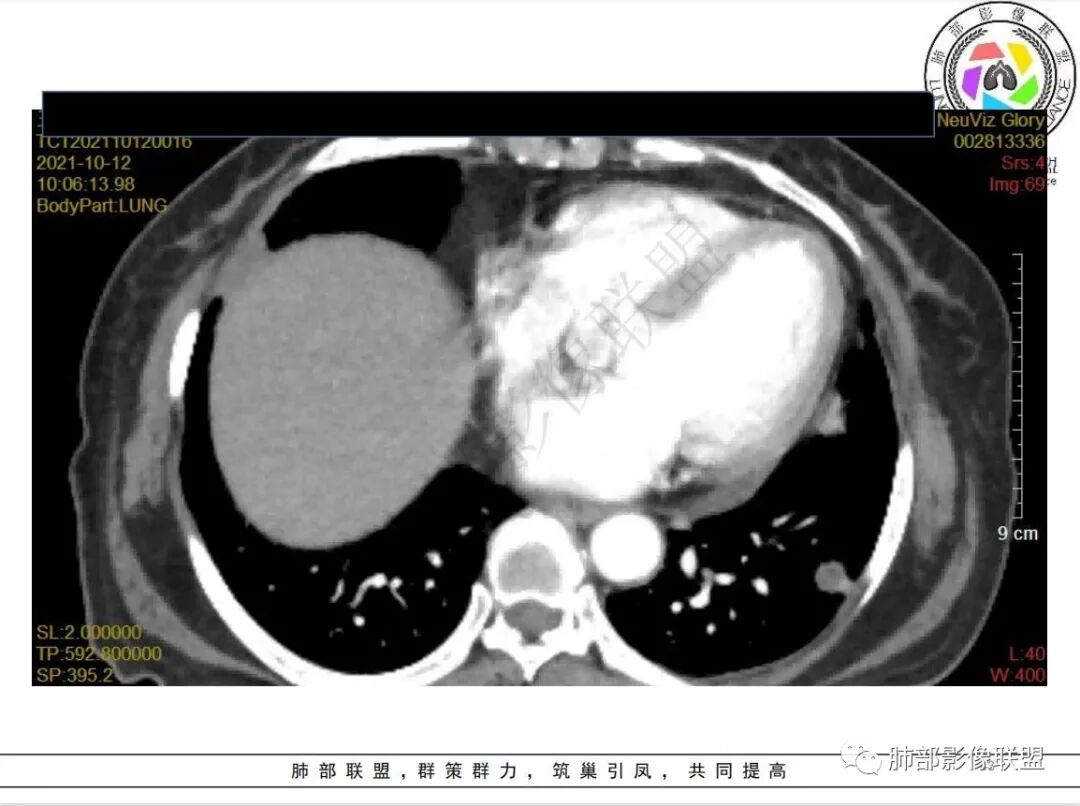

有白血病病史,免疫妥协,双肺多发结节,纵隔增大淋巴结,短期抗炎治疗后复查,病灶明显增大,右肺门肿块,内可见坏死,临近肺动脉受侵,支气管闭塞,周围见阻塞性炎症,考虑感染性病变,毛霉菌可能大

4.白血病化疗后,CT上出现多发结节,边缘可见晕征,病灶内可见多发坏死,右肺中叶肺动脉可见充盈缺损,右肺中叶可见融冰征,右肺中叶肺动脉侵犯栓塞伴右肺中叶肺梗死,可符合真菌感染。

血管侵袭性曲霉病是最常见的类型,其特征是真菌菌丝侵入和阻塞中小肺动脉,形成凝固性坏死、肺泡出血或出血性梗死。

6.肺曲霉病典型的CT表现是结节周围有磨玻璃样的晕征表现,或胸膜为宽基底的楔形实变。晕征表现为曲菌感染的肺结节伴梗死和凝固性坏死,周围有肺泡出血。最终可出现空泡征象,并可观察到中央坏死组织与周围肺实质分离形成空气新月征。